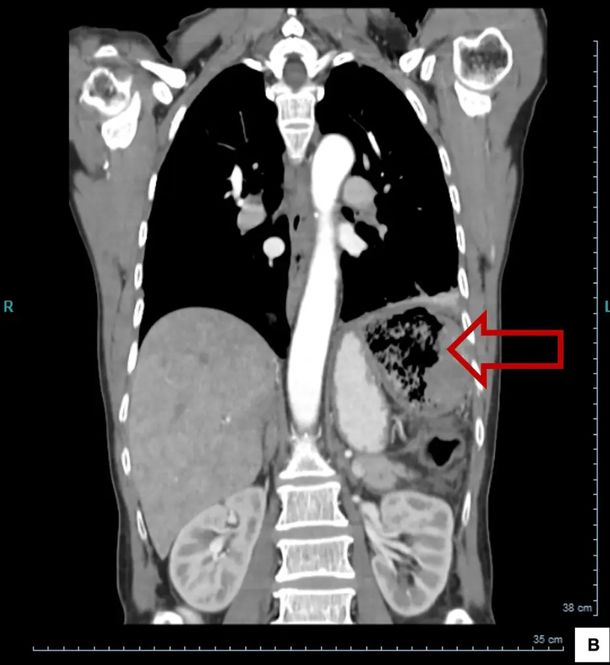

Alarmada por la aparición repentina de los síntomas, la paciente acudió al hospital, donde las ecografías revelaron una gran gasa en el abdomen. Los médicos creían que el polizón pegajoso se había quedado en su colon durante la operación dos décadas antes.